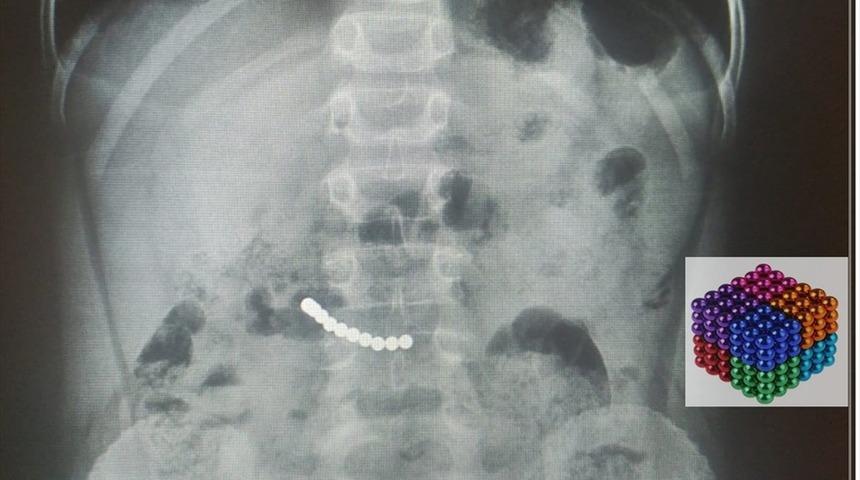

Muğla'da bir çocuğun midesinden çıkan mıknatıslar doktorları şaşırttı. Karın ağrısı şikayetiyle Muğla Eğitim ve Araştırma Hastanesine başvuran 7 yaşındaki U.K'nın kontrollerinde midesinde mıknatıs olduğu belirlendi.

Yaklaşık iki saat süren operasyonla çocuğun midesindeki 11 mıknatıs çıkarıldı.

Ekibiyle operasyonu gerçekleştiren hastanenin Çocuk Cerrahisi Ana Bilim Dalı Öğretim üyesi Prof. Dr. Süleyman Cüneyt Karakuş, bazı çocuklarda bu durumun ölümlere kadar giden sonuçlar doğurabileceğini belirterek, "Bazen küçük şeyler çocukların dikkatini çekebiliyor. Hastamızda mıknatısların midede yer değiştirmemesi, ameliyat kararı vermemizde etkili oldu." ifadesini kullandı.